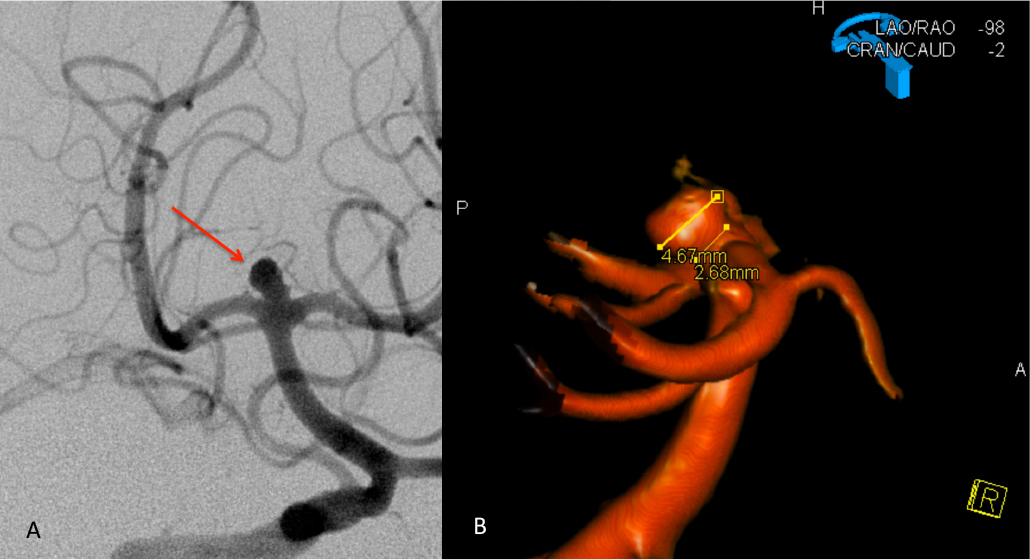

Urgent Cerebral Angiography confirmed a 5 mm posteriorly projecting aneurysm of the Basilar Artery Apex (Figure 2 A, B). Based on the location, morphology, and posterior projection, we decided to proceed to coil embolization of this high-risk aneurysm to prevent catastrophic re-bleeding and afford us the opportunity to maximize critical care for this patient during his hospital course. In this aneurysm, the dome-neck ratio was favorable from primary coiling, which was successfully performed resulting in near-complete embolization of the aneurysm (Figure 3 A, B). After 2 weeks of continued critical current l, endovascular, and neurosurgical care for complications of subarachnoid hemorrhage, including vasospasm and hydrocephalous, he was able to make a complete recovery and ultimately discharged home to complete his recovery, having regained all neurologic functions and activities of independent daily living and planning a return to work as an executive professional in the near future.

Figure 2: A) AP DSA angiogram demonstrates a 5 mm posteriorly projecting aneurysm of the Basilar Apex B) 3D DSA confirms the morphology and favorable dome to neck ratio for primary coil embolization.